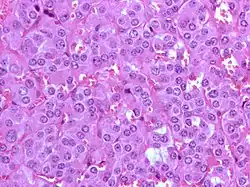

Guz chromochłonny zbudowany jest z feochromocytów (komórki chromochłonne) prawidłowo tworzących rdzeń nadnerczy (jest to główne miejsce występowania tych komórek, ale mogą również występować pozanadnerczowo). Są one wieloboczne lub wrzecionowate, brązowo-czarne po barwieniu dwuchromianem potasu, pochodzą z grzebienia nerwowego. Pod wpływem pobudzenia współczulnego wydzielają katecholaminy. Komórki tworzą gniazda (niem. Zellballen) w bogato unaczynionym zrębie.

Niektórzy autorzy z uwagi na budowę histologiczną klasyfikują guzy chromochłonne na 3 typy[10]:

- Guzy nabłonkowe – zbudowane z komórek nabłonkowych, zawierające ziarnistą, kwasochłonną cytoplazmę i hiperchromatyczne jądra; komórki układają się w sznury i skupienia.

- Guzy wielokształtne – zbudowane z komórek nabłonkowych, ale o większym stopniu zróżnicowania (obecne nawet komórki olbrzymie) i większej hiperchromatyczności.

- Guzy wrzecionowate – przeważają komórki wrzecionowate; jest to najrzadsza postać.